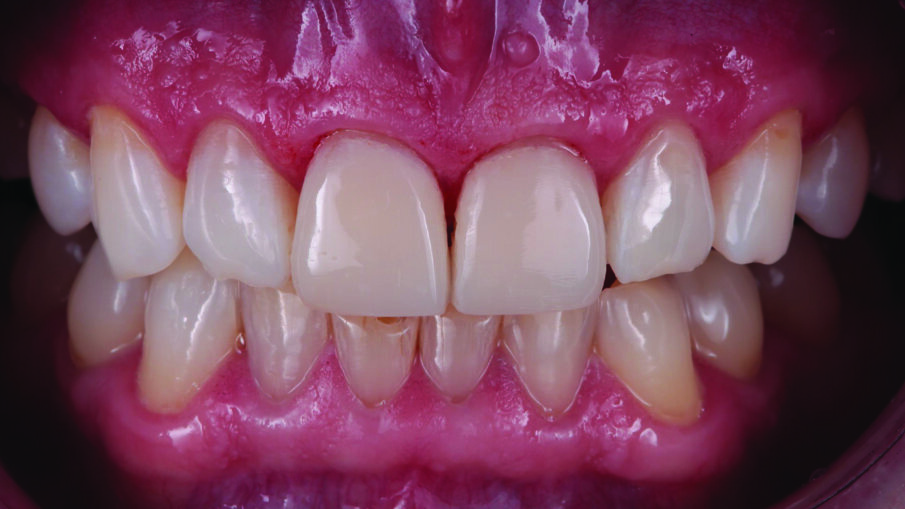

Outcome

The patient was happy with the treatment outcome. Three things were achieved with minimal effort. The discolorations were masked, the teeth were restored to their natural shape and the shade blended naturally with the adjacent teeth.

Treatment outcome immediately after rubber dam removal. The discolorations were gone, the restorations and the adjacent teeth had a similar shade, and a natural shape was achieved.